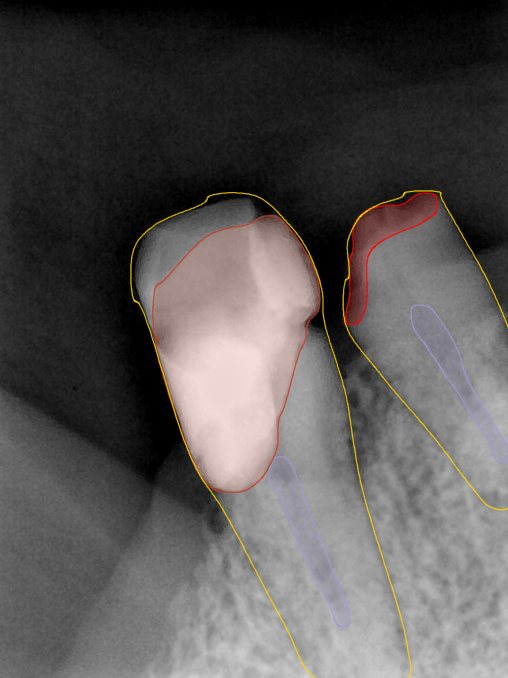

CR/DR 牙齿分割阶段记录

当前进展

- 完成了 CR/DR 牙齿相关分割训练

- 当前结果已经达到阶段预期,但仍有细节问题需要继续处理

相关测试

遇到的问题

- 训练过程中出现过 mask 下移问题

- 部分结果会出现 box 填充异常

- mask 边缘仍然有比较明显的锯齿感

第二版算法问题测试

Updated: 2026-04-13(更新日期)

| 第一版 | 第二版 | 是否解决 | |

|---|---|---|---|

![]() | ![]() ![]() 边角识别有问题 龋齿识别不全 牙髓识别不全 | ![]() | 解决 |

![]() | ![]() 边角识别有问题 识别信息有误 自查(牙冠识别不全) | ![]() | 解决 |

![]() | ![]() ![]() 边角识别有误 大范围填充识别遗漏 | ![]() | 解决 |

![]() | ![]() 识别信息不全 | ![]() | 解决 |

![]() | ![]() ![]() 边角问题 牙胶识别不全 牙冠识别不全 | ![]() | 解决 |

![]() 换图片 | ![]() | ![]() 牙冠部分稍微白了一些就识别成小范围修补,部分判断异常 | 部分解决,修复类略敏感,牙冠部分稍微白了一些就识别成小范围修补,部分判断异常。 |

![]() | ![]() ![]() 牙冠识别不全 牙髓不全 根尖炎龋齿识别有误 | ![]() | 解决 |

![]() | ![]() | ![]() | 解决 |

![]() 换图片 | ![]() | ![]() | 解决 |

![]() | ![]() 牙冠识别有误 | ![]() | 解决 |

![]() 换图片 | ![]() ![]() 边角识别有误 | ![]() 修复类敏感 | 部分解决,图像过白,导致修复类判断异常。 |

![]() 换图片 | ![]() 牙冠识别不全 | ![]() 修复类敏感 | 部分解决,图像过白,导致修复类判断异常 |

结论:修复类出现了不鲁棒的情况,后续需要加入轮廓的扩充数据进行增强。